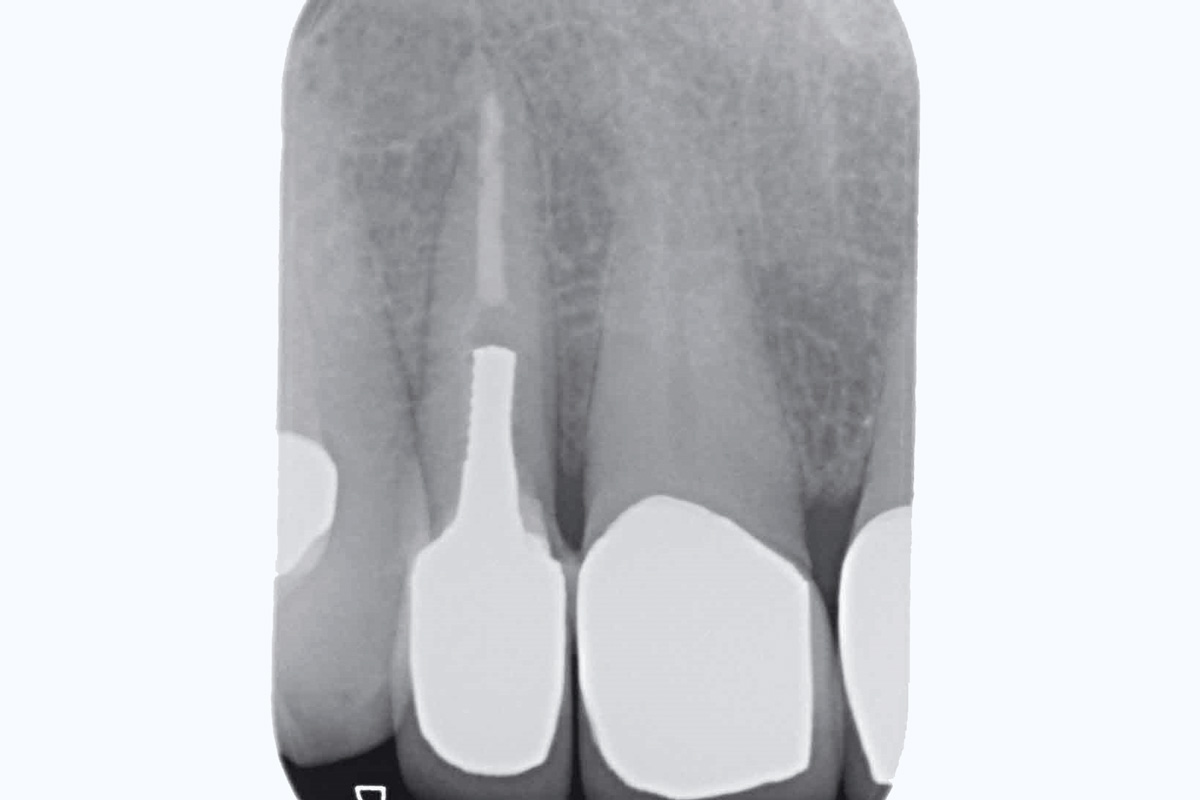

1/19 - Initial situation: Inflammated tooth #12Bone augementation with maxresorb® - Dr. R. Cutts

2/19 - Initial situation: x-rayBone augementation with maxresorb® - Dr. R. Cutts

Initial situation: Inflammated tooth #12